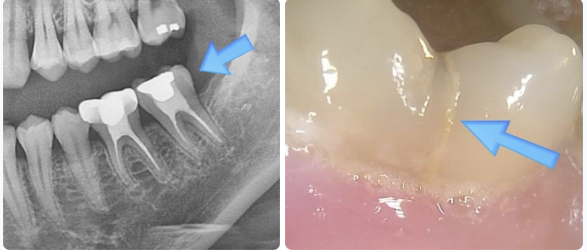

왼쪽 사진처럼 크라운치료를 진행하지 않은 채 사용하셨고, 그 결과 오른쪽 사진에서 보이는 것처럼 치아에 균열이 발생한 상태였습니다.

사진에서 확인되듯이 환자분께서는 치아가 ‘뚝’ 하고 갈라지는 듯한 느낌을 받았다고 말씀하셨습니다.

겉으로는 금이 관찰되지만, 통증이나 뚜렷한 염증 반응은 크지 않은 상태였습니다.